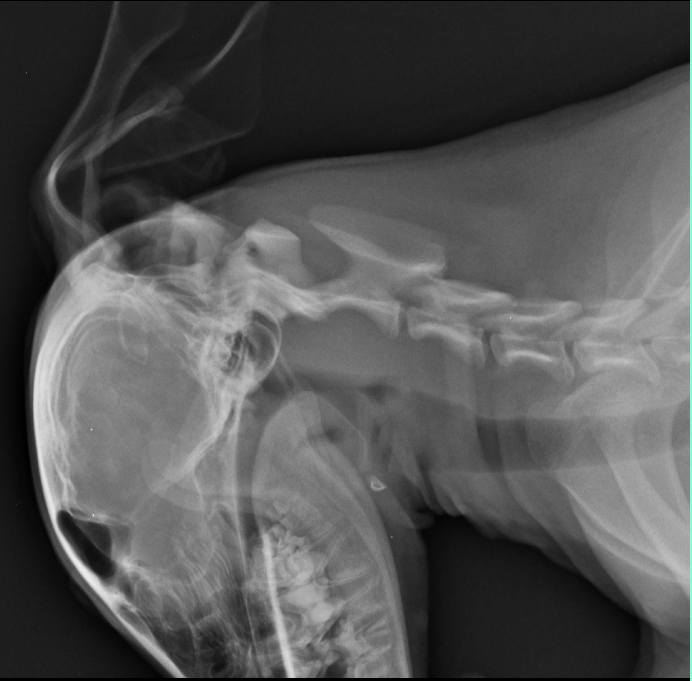

A subluxação atlantoaxial ou instabilidade atlantoaxial, é uma afecção articular onde ocorre o deslocamento dorsal do áxis (C2) em relação ao atlas (C1) levando a uma compressão da medula espinhal, podendo ser de forma congênita ou adquirida. Os cães acometidos apresentam sinais clínicos relacionados ao nervo motor superior (NMS) como consequência da compressão medular cervical, tendo curso agudo ou crônico, intermitentes ou não. O diagnóstico é realizado através da avaliação dos sinais neurológicos, exame clínico e exames de imagem. O tratamento pode ser médico, com o repouso, uso de colar cervical e utilização de analgésicos e anti-inflamatórios ou cirúrgico, visando a redução e estabilização permanente da articulação e eliminar a compressão medular. Este trabalho tem como objetivo relatar o atendimento a um canídeo, fêmea, sem raça definida, com 6 meses de idade e 6 kg, atendido no hospital veterinário do Centro Universitário Ingá, apresentando cervicalgia, relutância ao movimento de cabeça e pescoço, ataxia, quedas ao locomover-se e paresia de membros posteriores de curso agudo, tendo início a aproximadamente 2 dias tendo sido, através do exame radiográfico diagnosticada com Subluxação atlantoaxial congênita, tendo sido instituído tratamento conservativo com uso de colar cervico torácico e repouso em canil, tendo sido prescrito cloridrato de tramadol, dipirona, meloxicam e ranitidina, obtendo-se resposta satisfatória ao quadro, sem qualquer sinal recidiva durante 6 meses de acompanhamento.